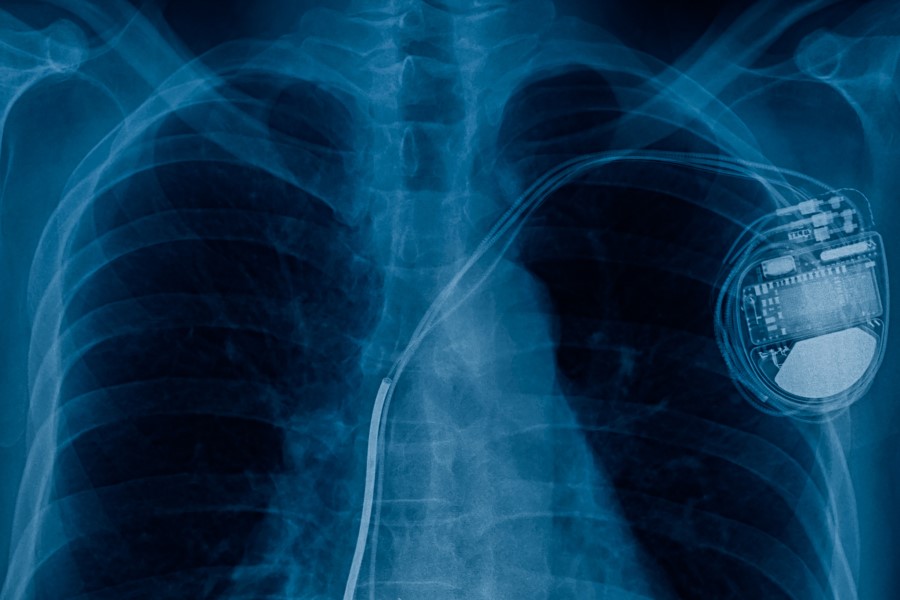

Rozrusznik serca jest niewielkim, elektrycznym urządzeniem wszczepianym przez kardiochirurga do mięśnia sercowego. Rozrusznik ma za zadanie pobudzić pracę serca, aby nadać mu prawidłowy rytm. Składa się ze stymulatora oraz elektrod, które wysyłają odpowiedniej mocy sygnały do serca, pobudzając jego rytm w przypadku zbyt wolnej akcji serca. Rozrusznik serca stanowi istotne narzędzie zarówno terapeutyczne, jak i diagnostyczne. Za pomocą elektromagnetycznej głowicy przykładanej w okolicę wszczepionego stymulatora kardiolog optymalizuje oraz ustawia indywidualnie parametry sprzętu dostosowane do potrzeb pacjenta. Zadaniem rozrusznika serca jest odczyt sygnałów sercowych oraz stymulacja pracy serca.

Operacja wszczepiania rozrusznika serca